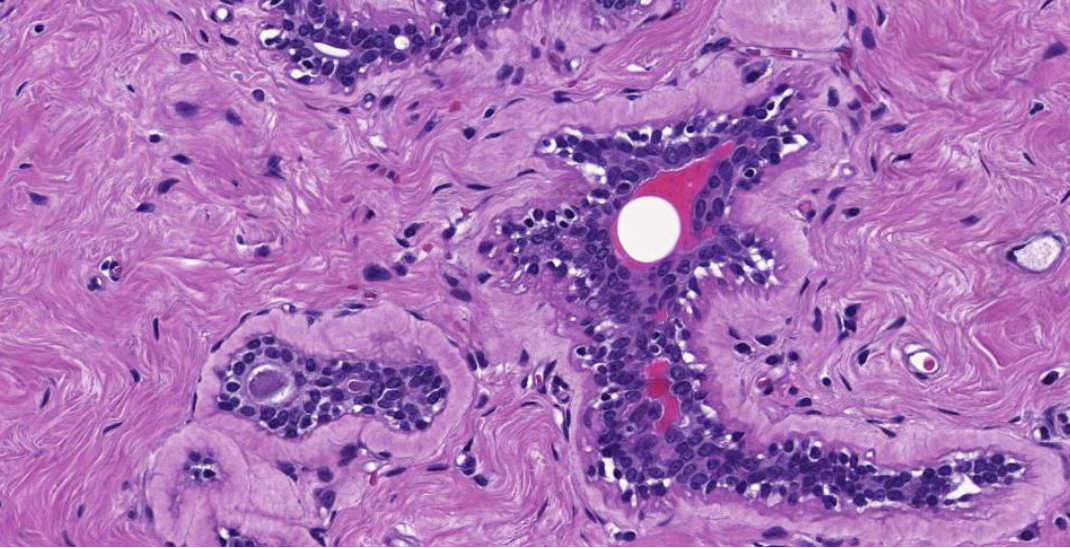

Diagnose?

Invasives unspezifisches duktales Mamma-CA